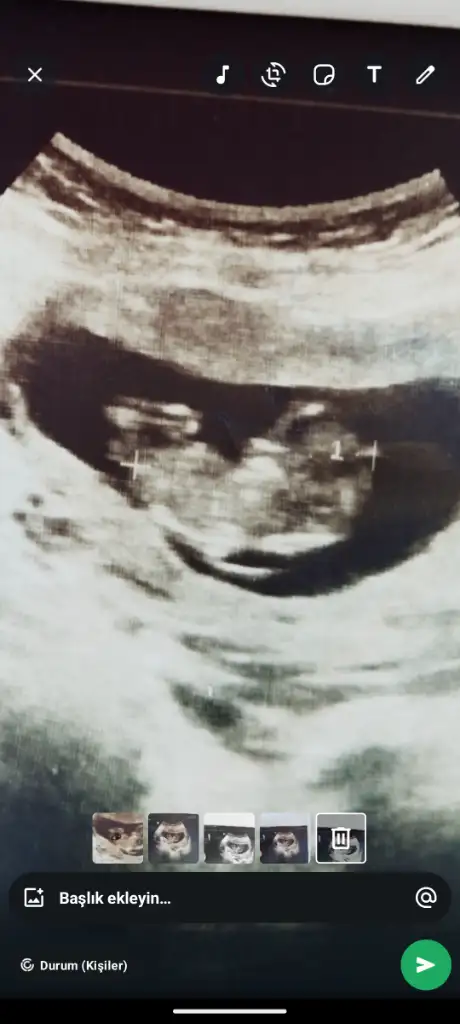

Yüz üstü durmuş sankiAy benimde 12 +1 bana da tahminde bulunabilir misiniz![]()

Evet yüz üstü yatıyor o yüzden doktorda bişey diyemedi belki sizin bi tahmininiz vardır diye sormak istedimYüz üstü durmuş sanki![]()

Belli oldu mu cinsiyetinizBende sizinle ayniyim 13+2 cuma günü gideceğim bakalım ne diyecek

Yok canım ya inşallah bir dahaki sefere düzgün pozisyon alır minik kuşEvet yüz üstü yatıyor o yüzden doktorda bişey diyemedi belki sizin bi tahmininiz vardır diye sormak istedim![]()